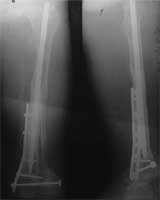

股骨远端骨母细胞瘤               段截肿瘤,大段异体骨移植术后3年,

骨愈合良好,并且获得良好的膝关节功能。